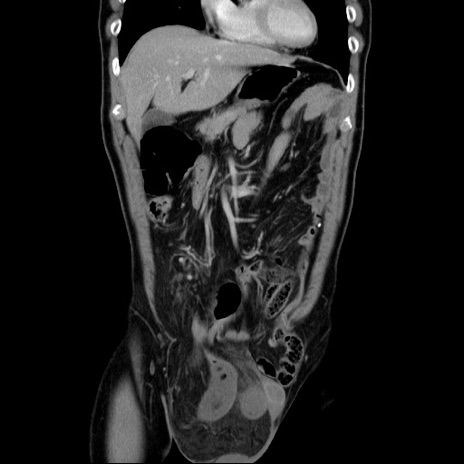

症例34(冠状断像)

【症例】60歳代 男性

【主訴】右鼠径部膨隆

【現病歴】1年程前より右鼠径部膨隆あり。自己にて還納可能だったため放置していた。3時間前より右鼠径部の脱出を認め、還納困難となり受診。

【既往歴】高血圧

【身体所見】右鼠径部に小児頭大の膨隆あり。弾性硬であり、用手還納は困難。左鼠径部にも膨隆を認める。脱出はなし。